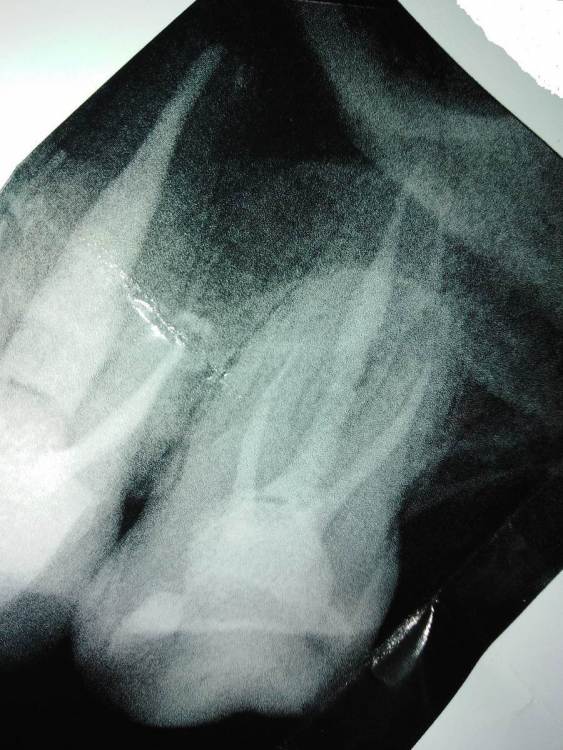

еатегsffhgj Опубликовано 20 марта, 2022 Поделиться Опубликовано 20 марта, 2022 здравствуйте. 3 года назад лечил зуб 7. сейчас в покое не болит,но есть реакция на горячее. попадает на зуб что то горячее и он очень сильно начинает болеть. языком не прикоснуться. через 5 минут боль проходит. и проходит,если выпить чего нибудь холодного. при постукивании в покое особо не отличается от остальных. врач говорит,что есть проблема с одним каналом. прямо не говорит,но видно,что не хочет связываться с этим зубом. подскажите,что с ним? врач меня уверяет,что таких симптомов этот зуб не может вызывать. Ссылка на комментарий

еатегsffhgj Опубликовано 21 марта, 2022 Автор Поделиться Опубликовано 21 марта, 2022 врач подозревает,что там инструмент сломан. боится,что не сможет его обойти. у меня во рту это уже 5 й зуб такой. почему вы их ломаете,то?? неужели нет материала,который не сломается? Ссылка на комментарий